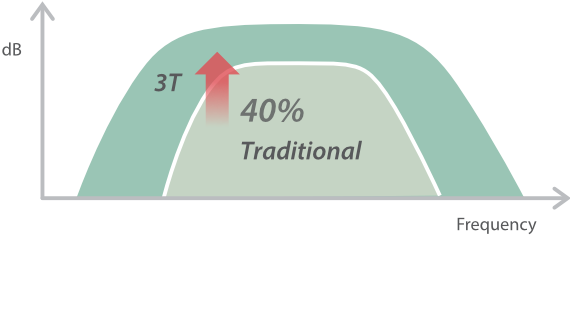

Based on the deep insights of customer needs, the DC-60 ECHO with X-Insight is designed to deliver high efficiency with precision imaging, which is empowered by eXpress Clarity, eXceptional Intelligence and eXceeding Experience.